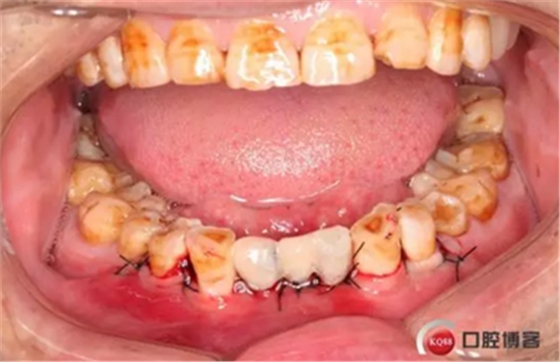

下圖是術(shù)前資料

患者,男性,47歲,全身情況良好,無手術(shù)禁忌,口內(nèi)因下前牙缺損松動(dòng)不美觀來院。初診檢查時(shí)發(fā)現(xiàn)患者前牙深覆合,下頜32、42缺失。31、41松動(dòng)二度,切緣磨耗嚴(yán)重,可探及髓腔,無保留價(jià)值。X-RAY檢查顯示:下頜前牙區(qū)寬度狹窄,咬合空間不足,無法行常規(guī)種植修復(fù).